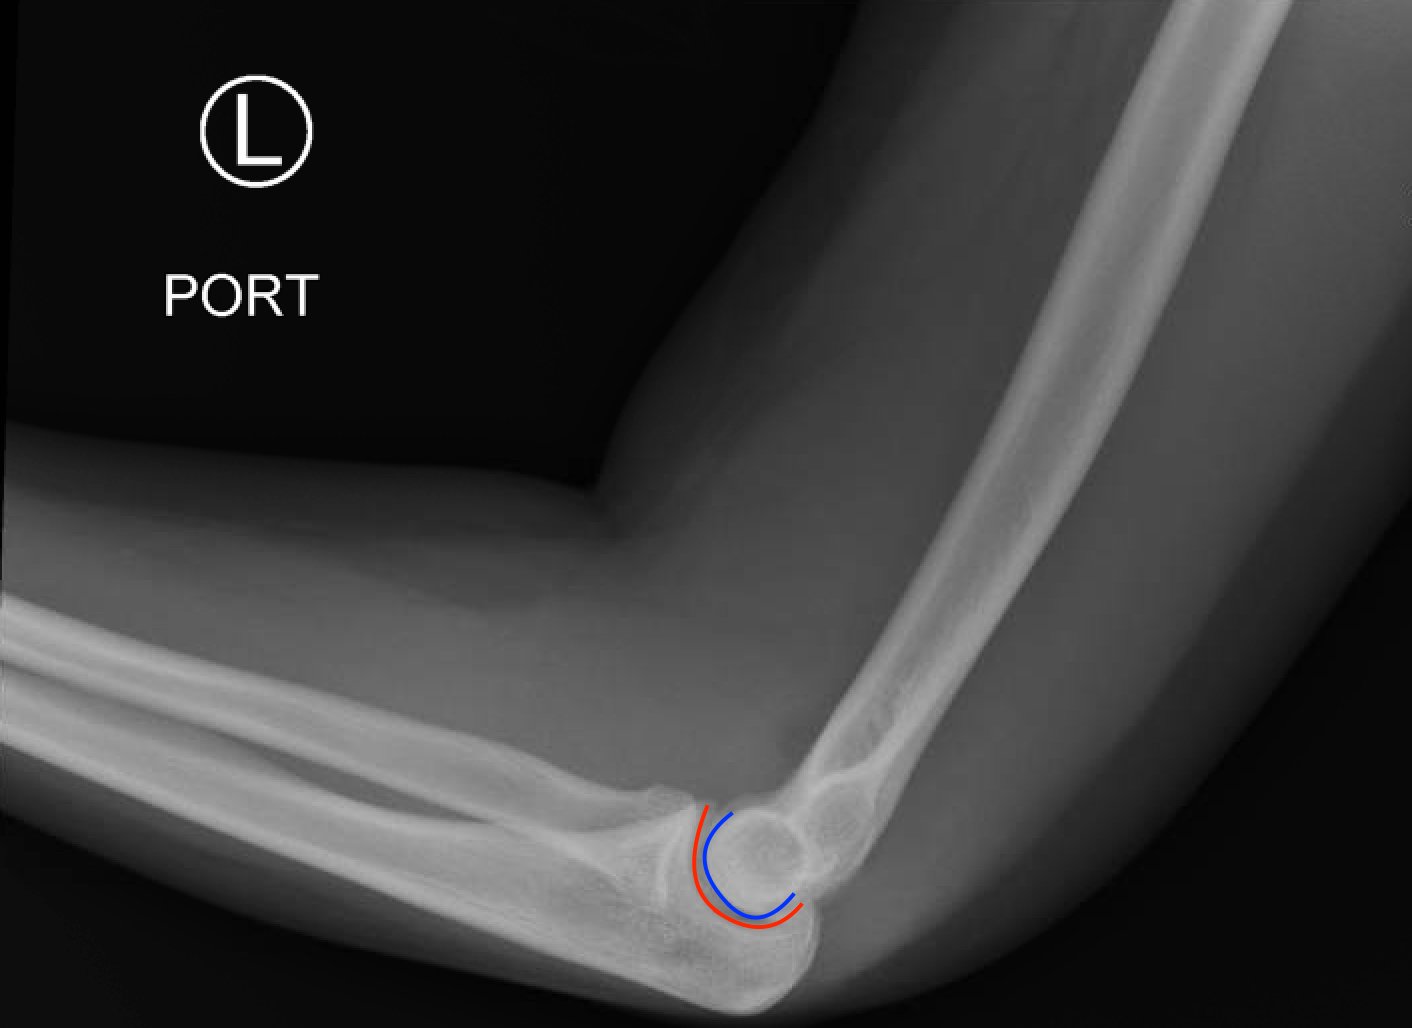

Posterior Elbow Dislocation, Lateral XRay, reduced, Annotated. JETem 2016